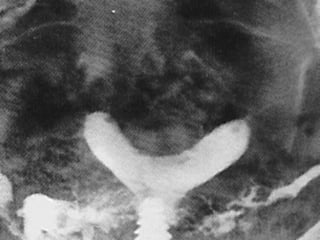

• 12.

Congenital Uterine Anomaly n Diagnosis: History Pelvic exam Hysterosalpingography U/S MRI Laproscopy Hysteroscopy IVP or U/S (Exclude Renal anomaly )

Congenital Uterine Anomaly

n  Treatment:

1- Double uterus (didelphic uterus): no need to treat.

2- Bicornate ut. --------- Strassmann procedure

( if indicated )

3- Ut. Septum --------- (BCP for dysmenorrhea ),

Tompkins metroplasty or Hysteroscopic resection of

septum )

4- Unicornate ut. -------- Surgery indicated if there is

blind horn which cause symptom----- surgical resection

of blind horn.